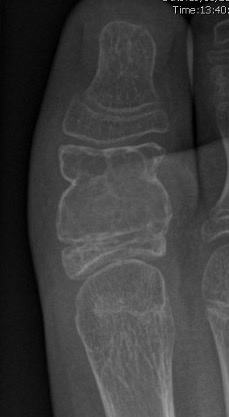

Giant cell tumour

Painful swollen foot / ankle

Lytic area on X-ray

Calcaneus > talus

Curettage and bone grafting